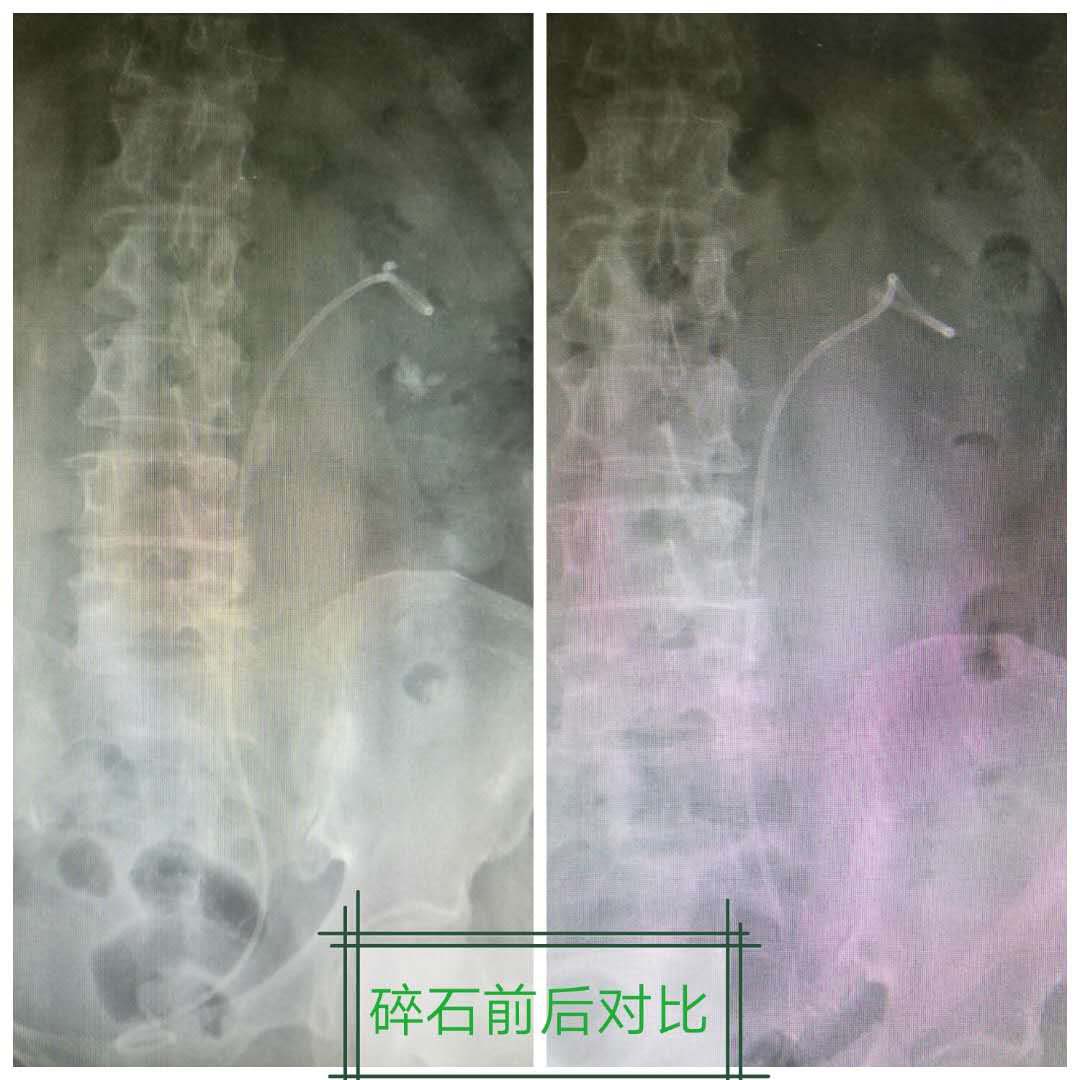

近日,东直门医院东区泌尿外科成功完成一例输尿管软镜激光碎石手术。

由于患者左肾内存在多发结石,容易造成再次梗阻,闫永吉主任决定对患者进行输尿管软镜下激光碎石取石治疗,彻底清除肾内结石,预防尿路梗塞,解决患者多年沉疴带来的痛苦。

手术过程十分顺利,患者术后3天即康复出院。